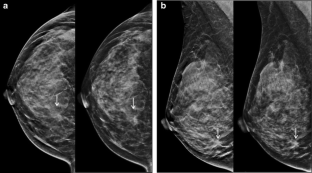

Fig. 1

Fig. 2